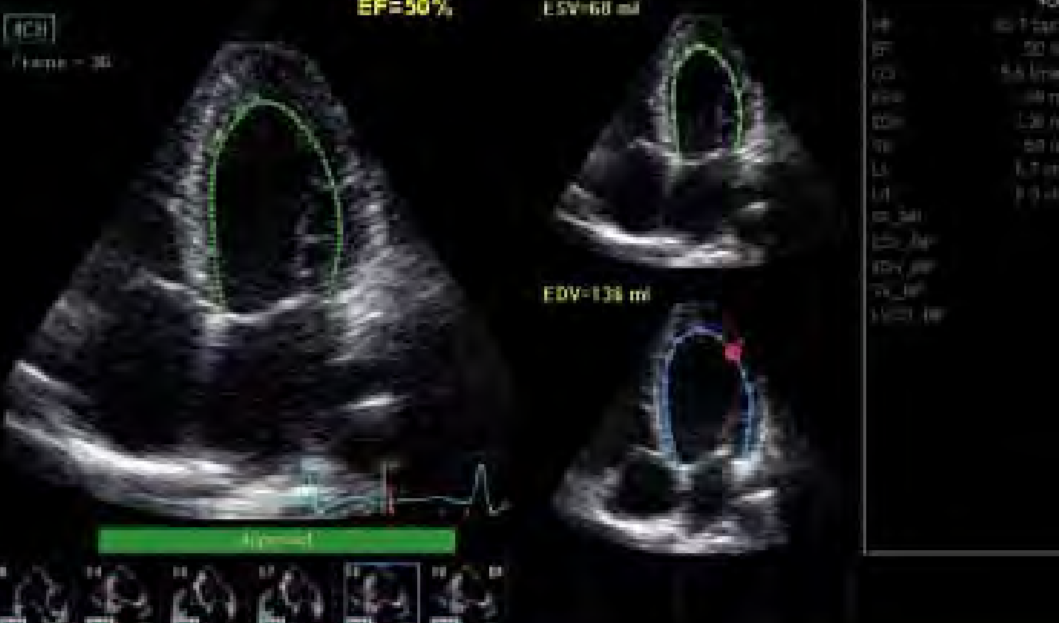

- Análisis y detallado informe de todos los datos vitales del sistema cardiovascular.

- Imágenes paramétricas que permite análisis cuantitativos para una ecocardiografía de mayor profundidad.